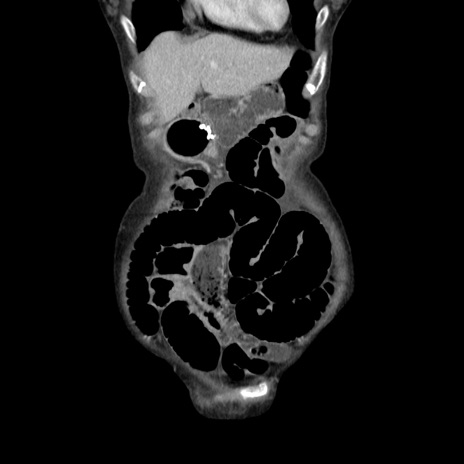

横断像